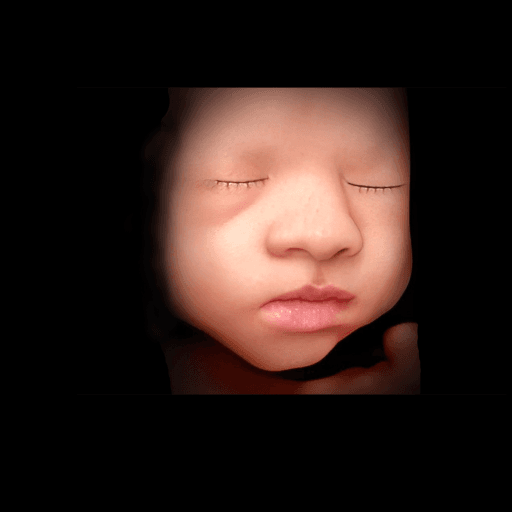

Tap a clip to play an animated ultrasound example.

Simply upload your 3D ultrasound image and proceed from there. Our system will guide you through the enhancement process step by step.